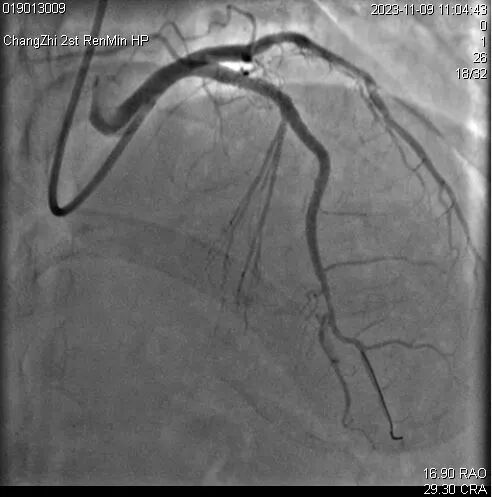

患者王某,女,58岁,既往高血压病史30年。糖尿病病史18年。脑梗死病史18年,言语迟钝。患者近10月反复心前区不适,2023年8月就诊于长治二院心血管内科,完善冠状动脉造影提示三支病变:前降支近中段弥漫性狭窄80-95%,回旋支远段闭塞,钝缘支近段闭塞。右冠近段弥漫性狭窄85-90%,后三叉开口前闭塞。

2023年11月支架植入术后造影